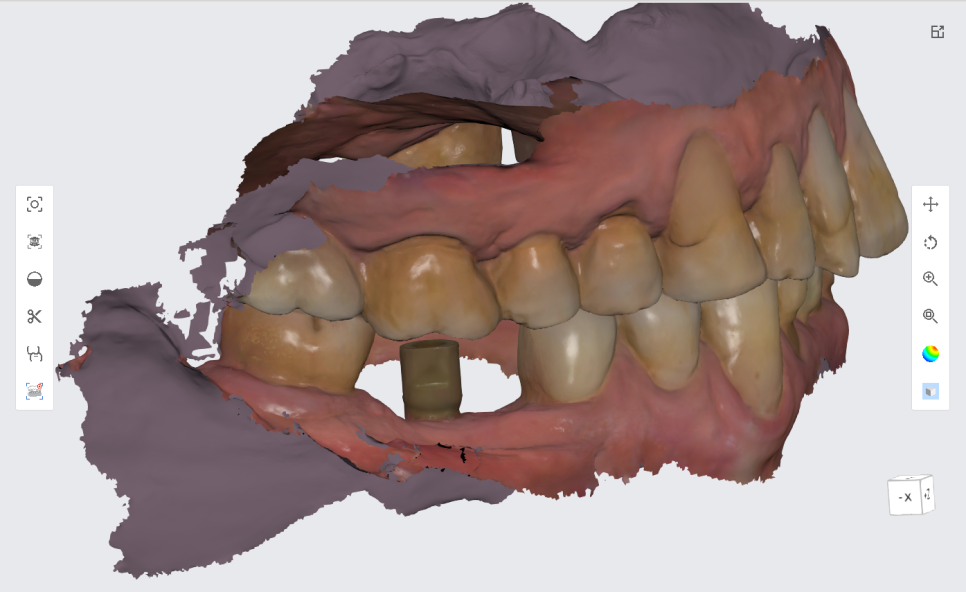

스캔된 3D 자료들을 잘 취합해서

본인이 가지고 있는 치아색과 유사하게

지르코니아 크라운을 만듭니다.

구강내에 딱 맞게 제작된 보철물은

임시로 한번 붙여드리고 입안에 들어갔을 때나

씹을 때 불편한게 없으신지 1주일 정도 테스트를 해봅니다.

이 테스트 기간에 볼 쪽에 둥근 손잡이를 달아놓는데요,

완전히 붙일 때 보철을 잡고 뺄 수 있도록 만든 손잡이입니다.

완전히 붙일 때는 깔끔하게 제거해 드리니 걱정하지 마세요~^^

파란색으로 보이는 부분은 조이는 나사가

임플란트로 들어가는 통로입니다